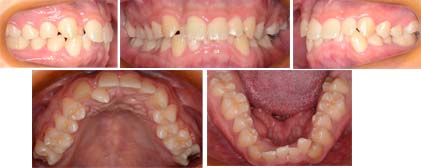

来院時の写真

かみ合わせが深く、上顎側切歯が完全にブロックアウトされています。また下顎前歯にも叢生があります。抜歯するかどうか悩みました。抜かずに治療を終える事ができました。

治療前には上下前歯の正中線はずれていましたが、治療後には合わせることができました。非抜歯、リンガルブラケットで治療しました。非抜歯に決断したのは横顔に問題のない顔立ちだったという事が大きいです。口もとが入ります。しかし、この患者様にはそれが必要ありませんでした。リンガルブラケット(裏側矯正)は力点が内側にあるので排列しても前歯が前に出ません。横顔が悪くなる事はありません。

排列する場所は不足していましたが、リンガルブラケット(裏側矯正)なら口元が出る事なく治療可能だと判断して非抜歯(歯を抜かない)治療を選択しました。内側にある側切歯を排列するのに時間がかかりました。